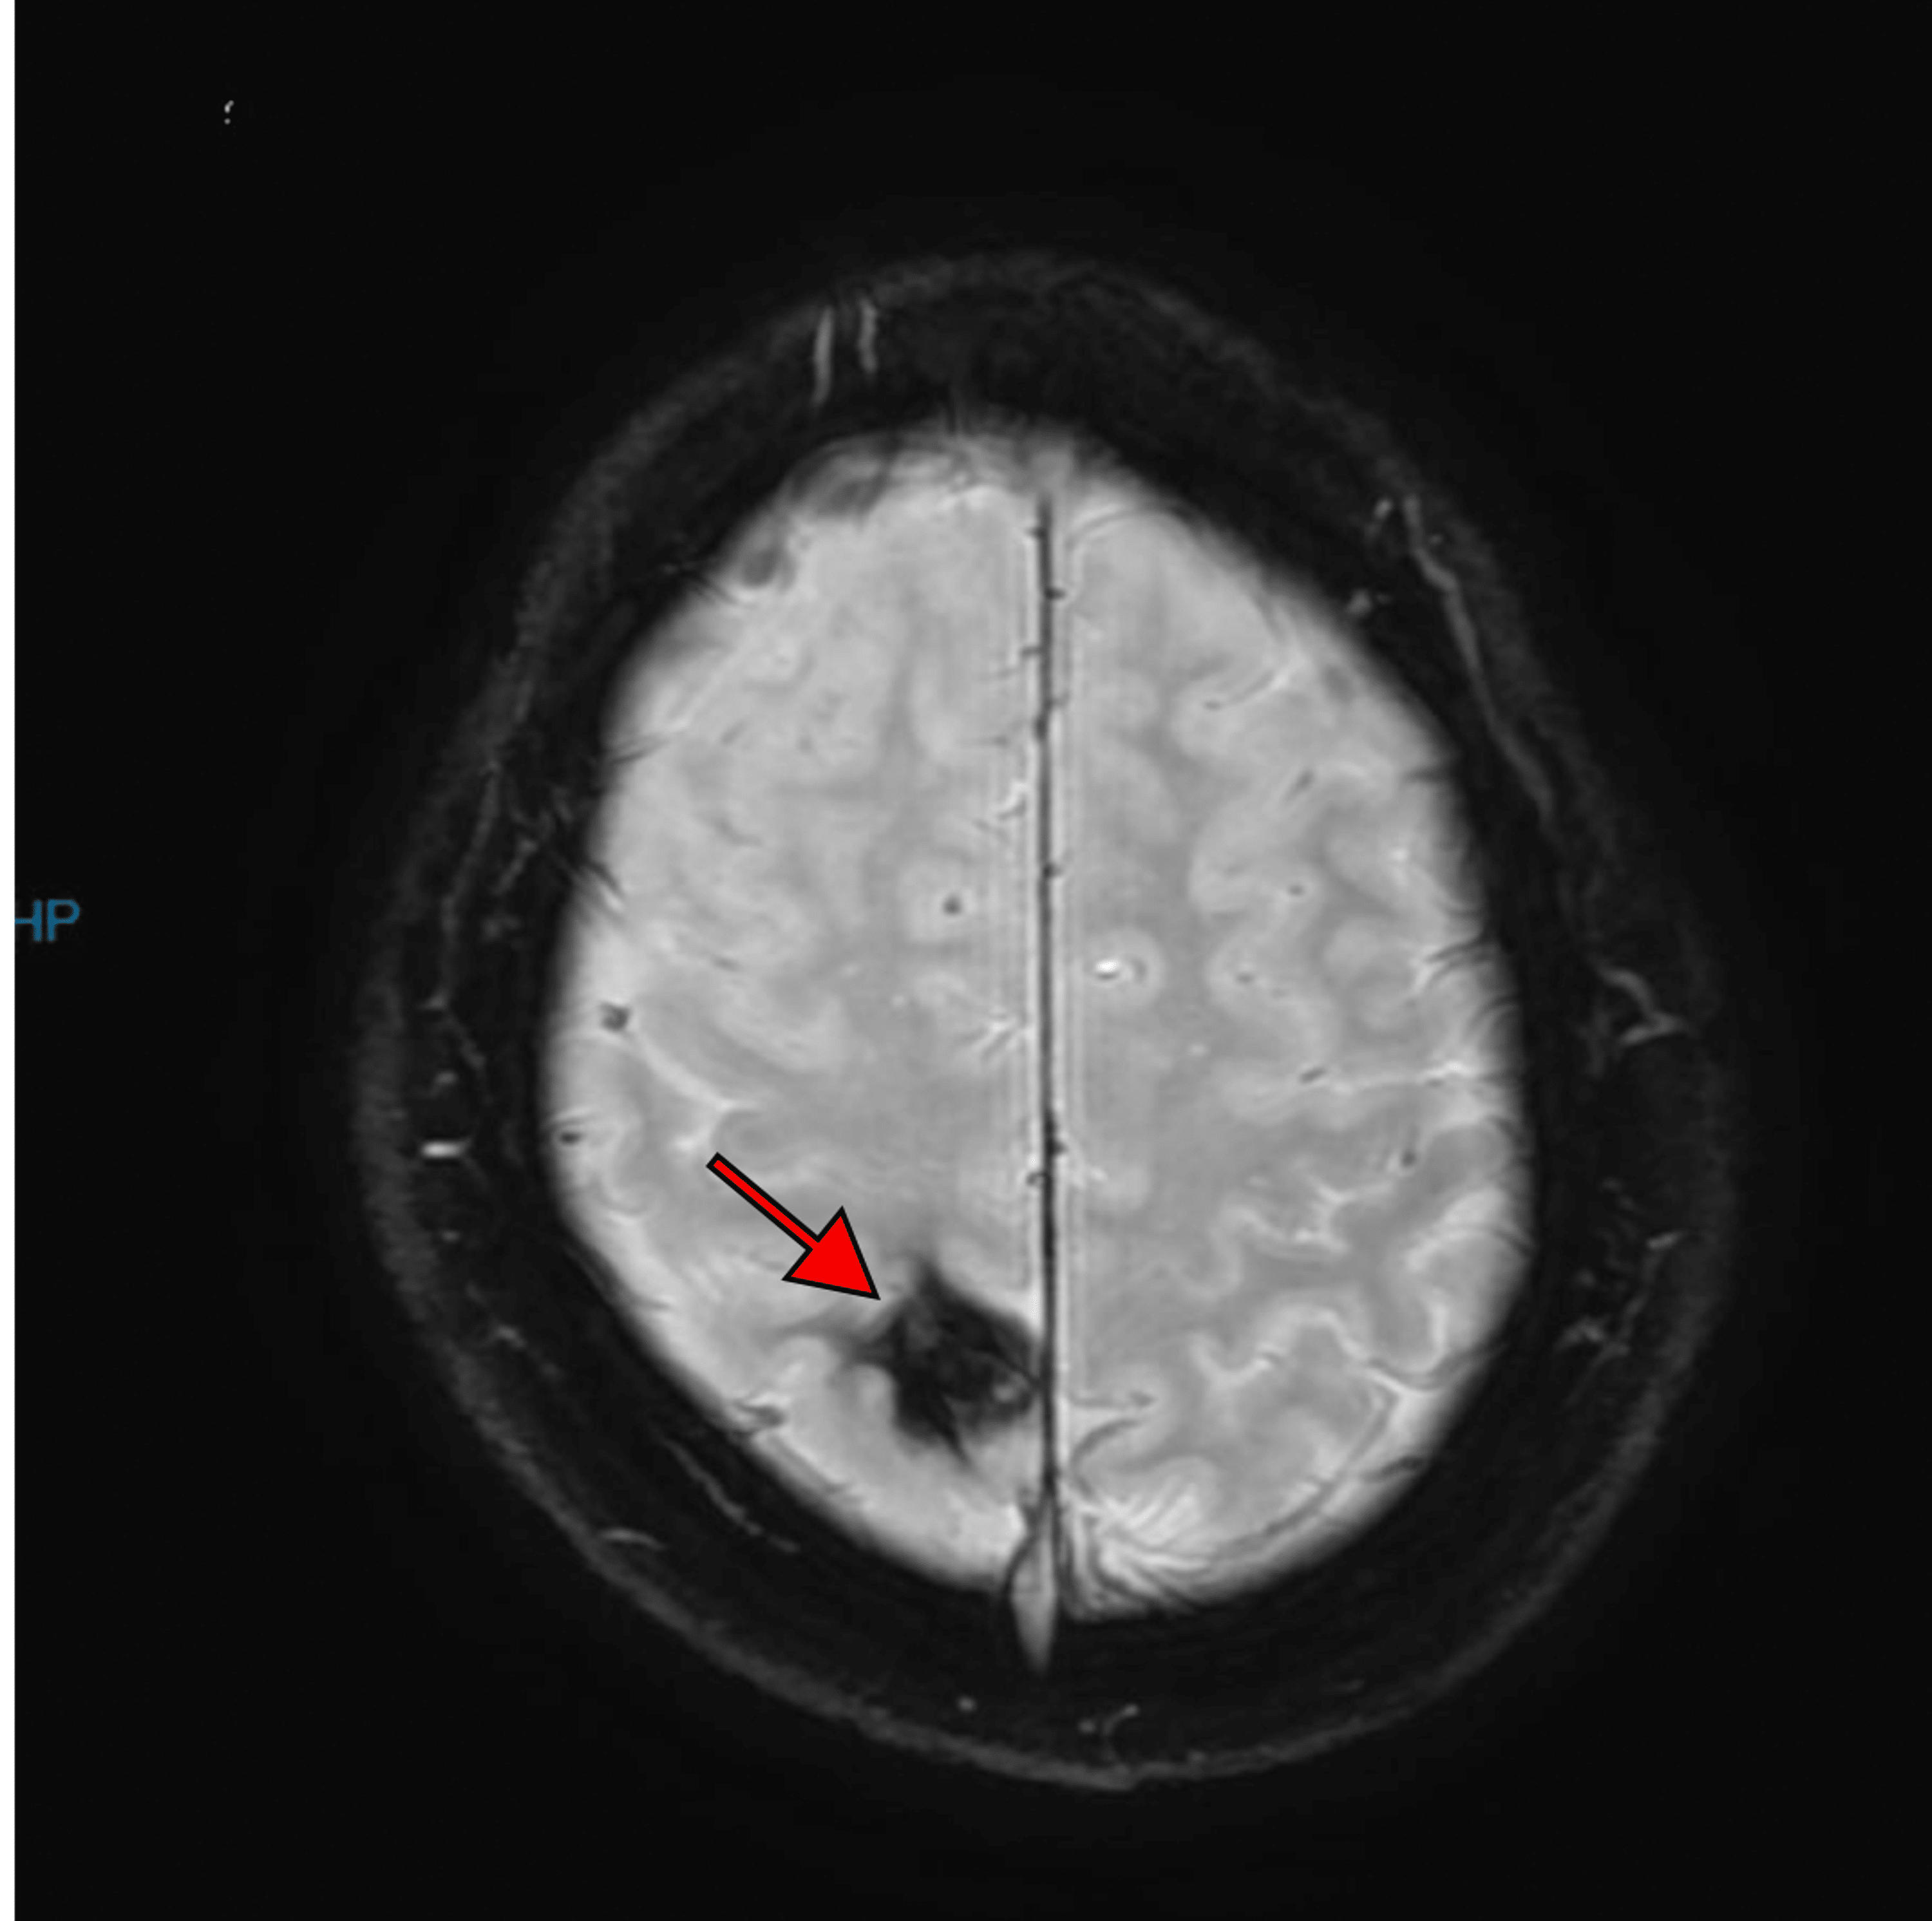

Blooming Artifact MRI

Blooming artefact. Significant artefact (arrow) obscuring the left What Does Blooming Artifact Mean abstract and figures. blooming artifacts have been attributed to the partial volume effect, motion artifacts as well as beam hardening. This review paper aims to summarize cardiac ct blooming artifacts, how they present clinically and what their root causes and. blooming artifact is a type of artifact that occurs in magnetic resonance imaging (mri) when there are. What Does Blooming Artifact Mean.

Cavernous Malformation The Neurosurgical Atlas What Does Blooming Artifact Mean image artifacts caused by cardiac motion appear in different ways, such as blurred edges of anatomies, double contours, distorted. blooming artifact is a susceptibility artifact encountered on some mri sequences in the presence of paramagnetic substances that affect the local magnetic. blooming artifacts have been attributed to the partial volume effect, motion artifacts as well as beam. What Does Blooming Artifact Mean.